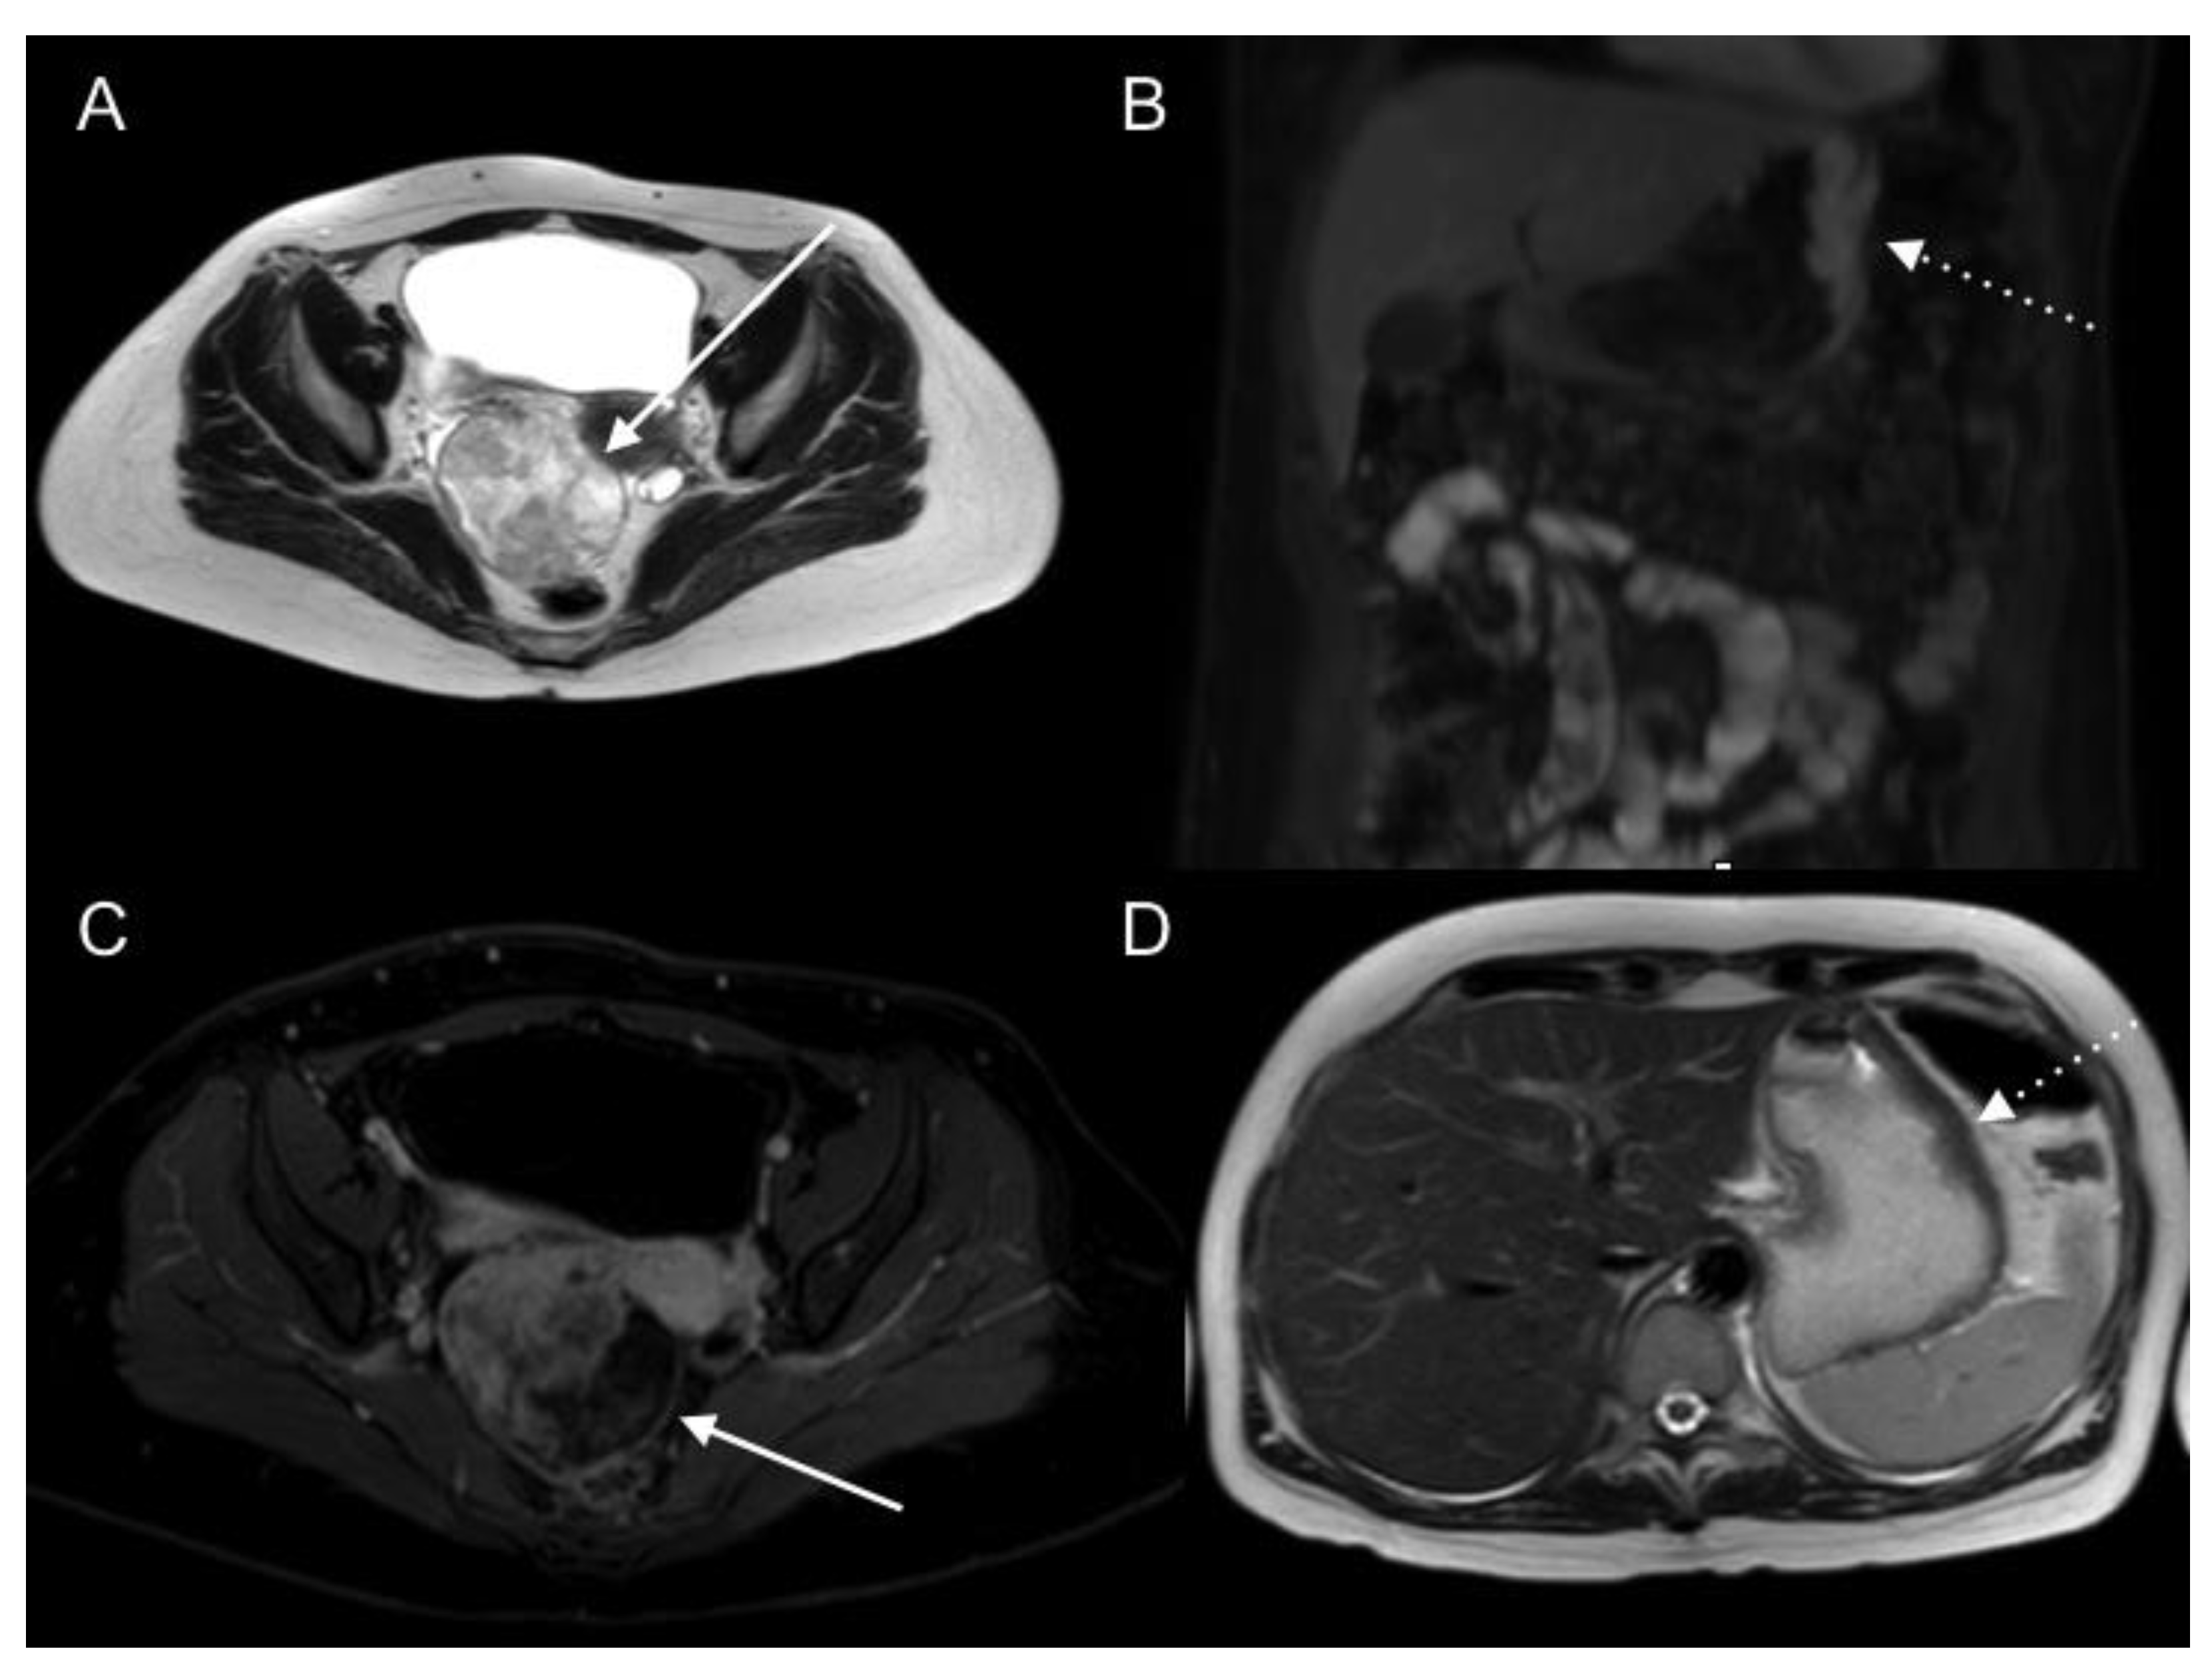

2.2. Magnetic Resonance Imaging (MRI)

| Bowel obstruction or partial obstruction at more than one site |

| Mesentery drawn together by tumour (clumped bowel) |

| Tumour infiltrating between leaves of the small bowel mesentery |

| Tumour ≥ 5 cm in diameter in jejunal regions |

| Mesenteric or para-aortic lymphadenopathy |

| Hydroureter |

| Psoas muscle invasion |

| Pelvis sidewall invasion |

| Seminal vesicle invasion |

| Hepatoduodenal ligament infiltration and/or bile duct obstruction |

| Tumour ≥ 5 cm in diameter in gastrohepatic ligament or subpyloric space |

| Gastric outlet obstruction |